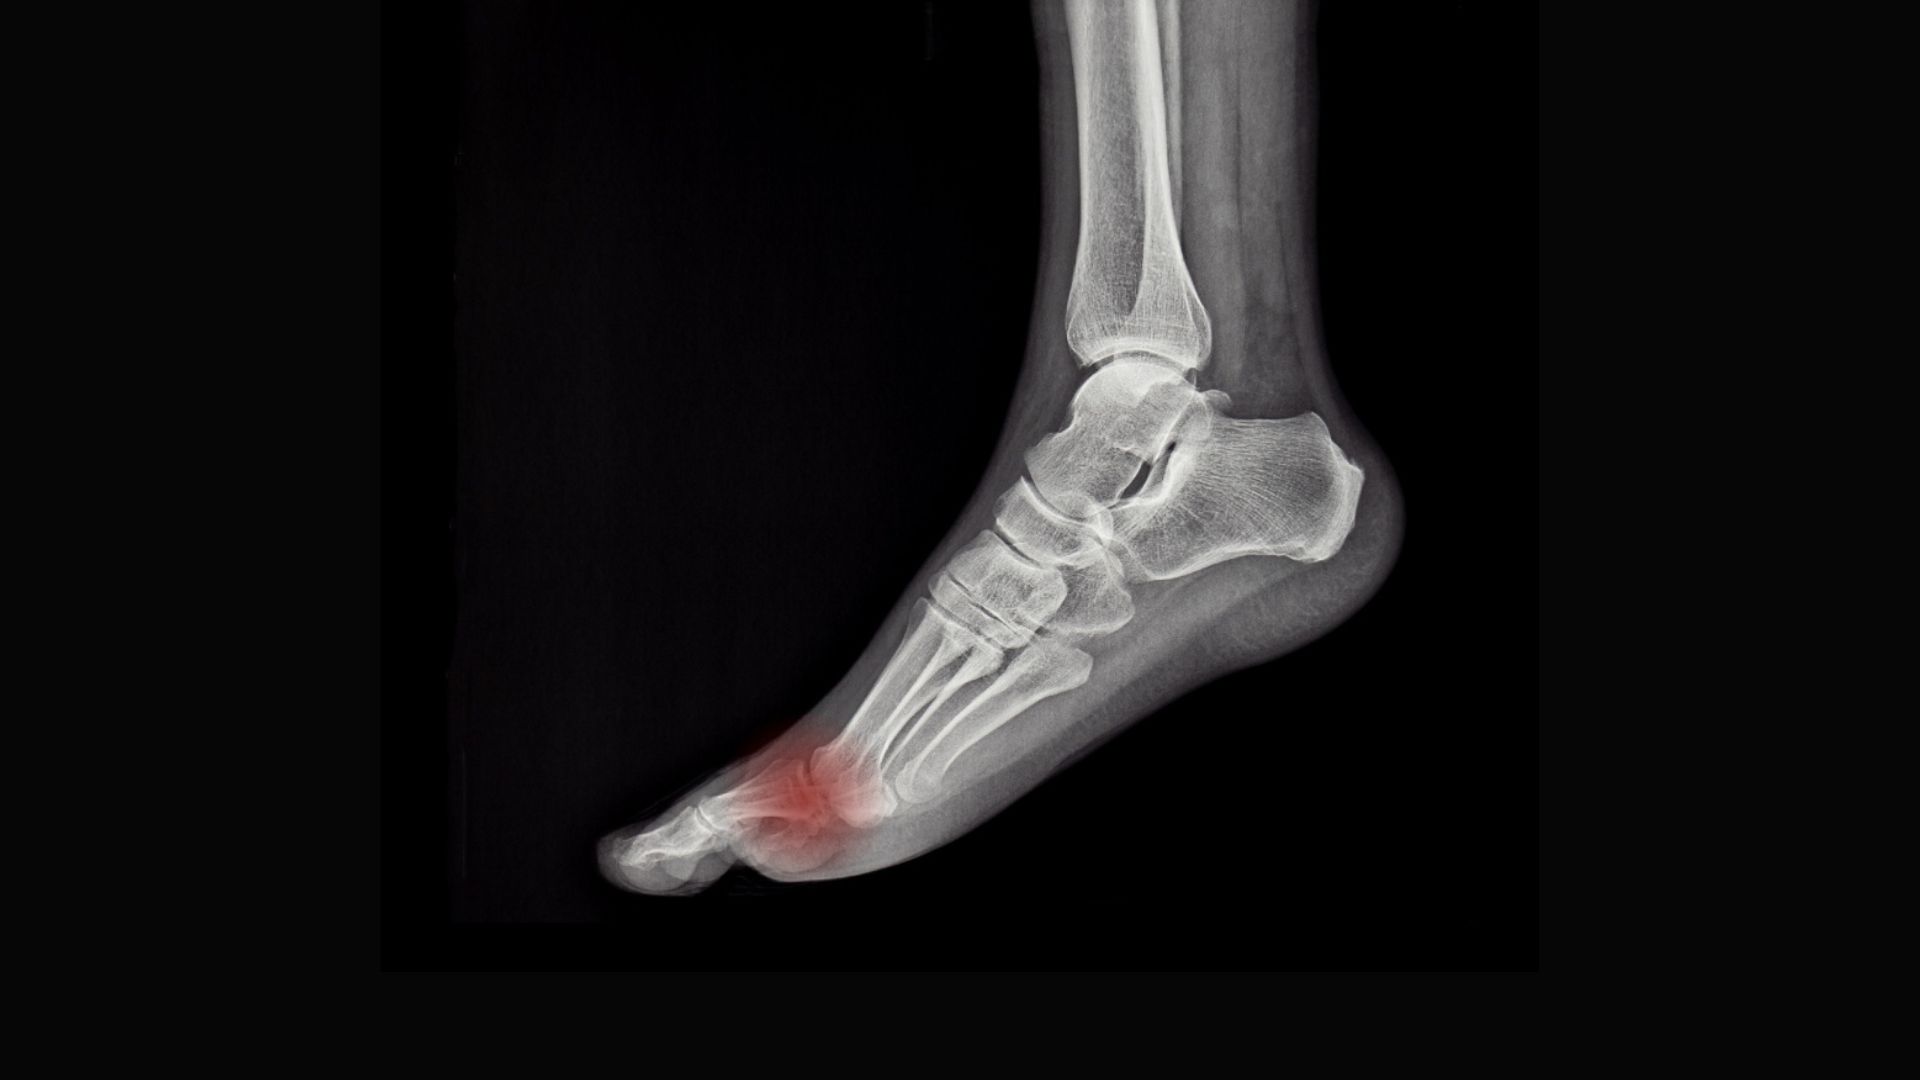

What if the root of your client’s knee, hip, or back pain starts with their big toe? What if overlooked midfoot restrictions are driving compensation up the kinetic chain? In this video demonstration, Erik teaches a series of simple, effective foot mobilizations you can easily integrate into your sessions.